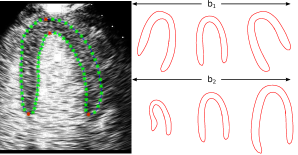

A statistical shape model of the myocardium is built from 89 manual annotations using PCA [2]. Each annotation has N=76𝑁76N=76 landmarks comprising 4 key landmarks with 18 landmarks spaced equally in between along the boundary of manual tracing (Fig. 1(a) left). The shape model is represented as:

where 𝒙𝒙\boldsymbol{x} is a 2N𝑁N-D vector containing the 2D coordinates of the N𝑁N landmark points, 𝒙¯¯𝒙\bar{\boldsymbol{x}} is the mean coordinates of all training shapes, 𝒃𝒃\boldsymbol{b} is a set of K𝐾K shape parameters and 𝑷𝑷\boldsymbol{P} contains K𝐾K eigenvectors with their associated eigenvalues λisubscript𝜆𝑖{\lambda}_{i}. K𝐾K is the number of modes and set to 10 to explain 98% of total variance so that fine shape variations are modeled while noise is removed. Values of bisubscript𝑏𝑖{b}_{i} are bounded between ±sλiplus-or-minus𝑠subscript𝜆𝑖\pm s\sqrt{\lambda_{i}} so that only plausible shape similar to the training set is generated (Fig. 1(a) right). Refer to [2] for details on statistical shape model.

Figure 1: (a) Left: A manual annotation from training set showing key landmarks (red) and other landmarks in between (green). Right: First two modes of variations of the shape model. (b) Left: Landmarks 𝒙𝒙\boldsymbol{x} (blue dots) generated randomly by the shape model in (1). Right: d1subscript𝑑1d_{1}(d2subscript𝑑2d_{2}) is the SM feature value measuring the signed shortest distance from pixel 𝒑𝟏subscript𝒑1\boldsymbol{p_{1}}(𝒑𝟐subscript𝒑2\boldsymbol{p_{2}}) to the myocardial boundary B(𝒙)𝐵𝒙B(\boldsymbol{x}) (blue contour). d1subscript𝑑1d_{1} is positive and d2subscript𝑑2d_{2} is negative.